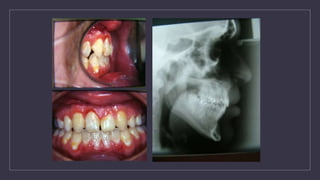

Orthodontic Treatment of Transitional

Dentition

• The purpose the dentition adjacent to cleft has to be orthodontically repositioned to

prepare the cleft side for the secondary alveolar bone graft

• Preparing the maxillary arch for a bone graft (6-12 months) :

1. Bonded edgewise appliance

2. Supported with a maxillary expander quad helix expander

Orthodontic Treatment For Permanent Dentition

Orthodontic Treatment ofTransitional Dentition • The purpose the dentition adjacent to cleft has to be orthodontically repositioned to prepare the cleft side for the secondary alveolar bone graft • Preparing the maxillary arch for a bone graft (6-12 months) : 1. Bonded edgewise appliance 2. Supported with a maxillary expander quad helix expander